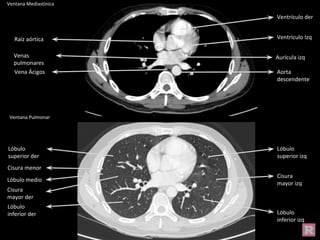

Ventana Mediastínica

Ventana Pulmonar

Aorta

descendente

Vena Ácigos

Aurícula izq

Ventrículo der

Raíz aórtica

Venas

pulmonares

Ventrículo Izq

Cisura

mayor izq

Lóbulo

inferior izq

superior izq

superior der

inferior der

Cisura menor

mayor der

Lóbulo medio